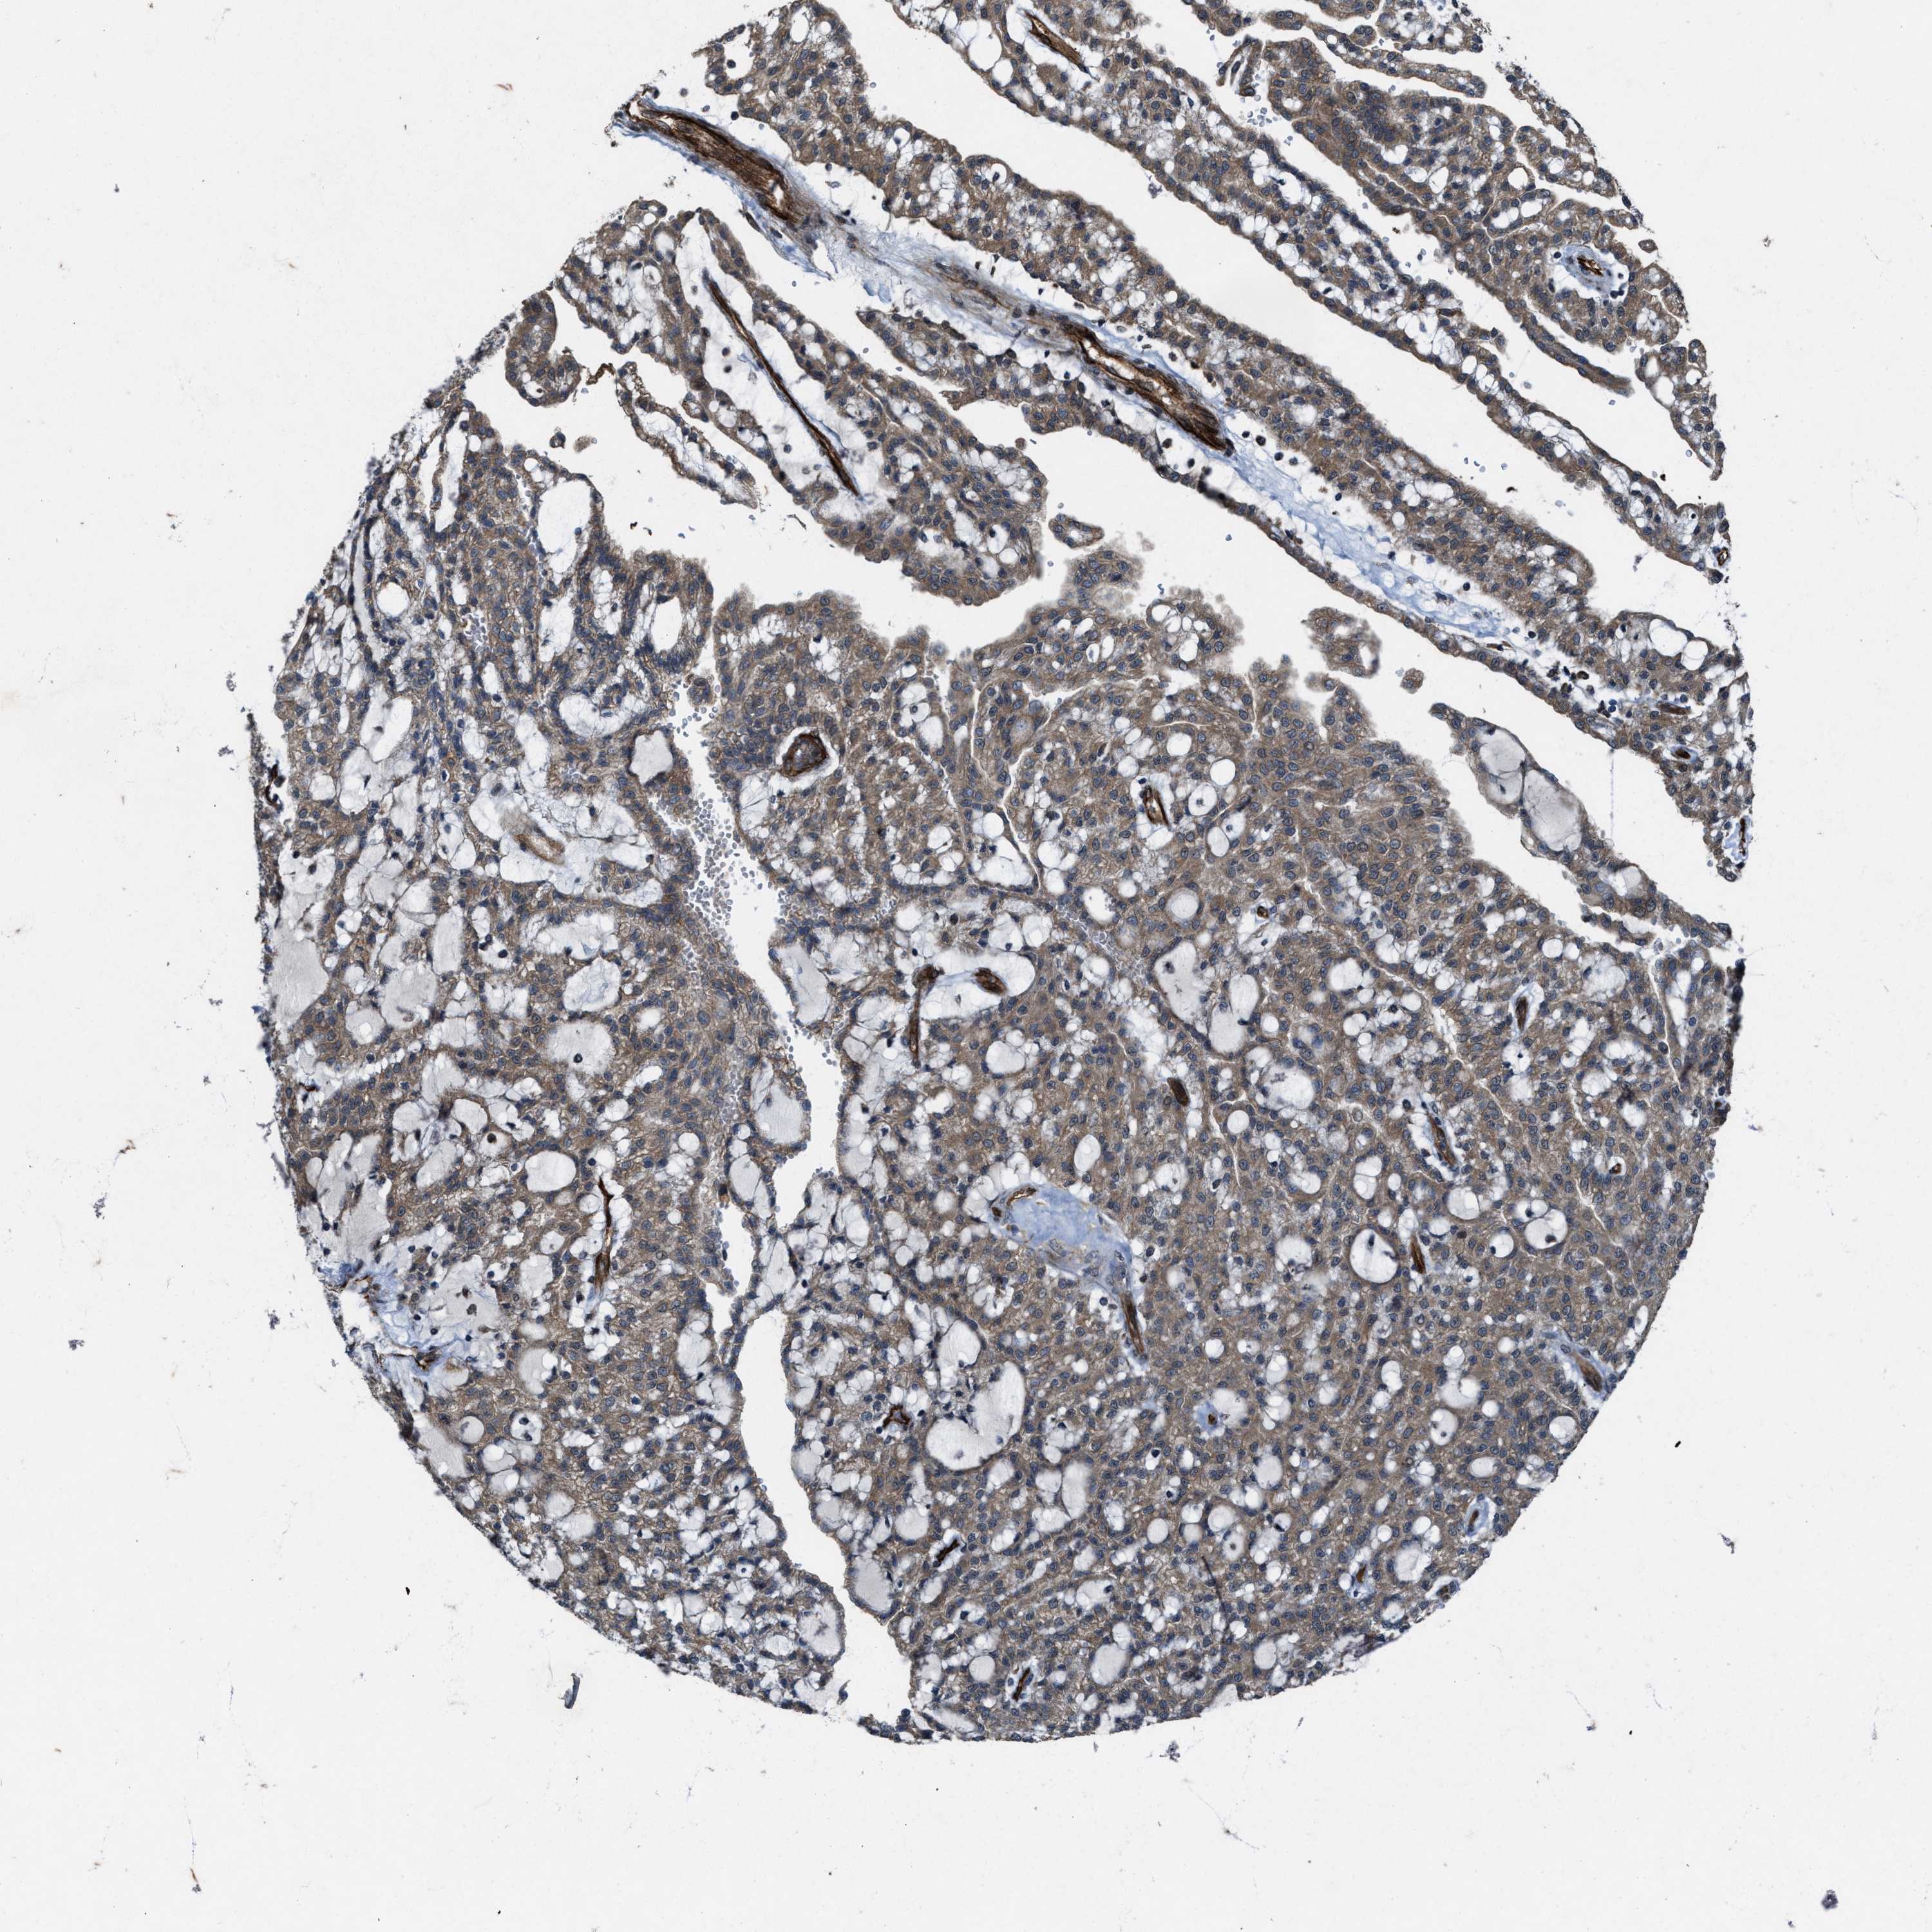

KIDNEY RENAL PAPILLARY CELL CARCINOMA (TCGA) - Interactive survival scatter ploti

The Survival Scatter plot shows the clinical status (i.e. dead or alive) for all individuals in the patient cohort, based on the same data that underlies the corresponding Kaplan-Meier plots. Patients that are alive at last time for follow-up are shown in blue and patients who have died during the study are shown in red.

The x-axis shows the expression levels (FPKM) of the investigated gene in the tumor tissue at the time of diagnosis. The y-axis shows the follow-up time after diagnosis (years). Both axes are complimented with kernel density curves demonstrating the data density over the axes. The top density plot shows the expression levels (FPKM) distribution among dead (red) and alive patients (blue). The right density plot shows the data density of the survived years of dead patients with high and low expression levels respectively, stratified using the cutoff indicated by the vertical dashed line through the Survival Scatter plot. This cutoff is automatically defined based on the FPKM cutoff that minimizes the p-score. The cutoff can be changed by dragging the vertical line or by entering a cutoff value in the square labeled "Current cut-off".

Under the Survival Scatter plot the p-score landscape (black curve; left axis) is shown together with dead median separation (red curve; right axis). Dead median separation is the difference in median mRNA expression between patients who have died with high and low expression, respectively. It is calculated as follows: median FPKM expression of dead patients with high expression - median FPKM expression of dead patients with low expression. This is intended to aid the user in visually exploring custom cutoffs and the associated p-scores and dead median separation.

Individual patient data is displayed and can be filtered by clicking on one or more of the category buttons on the top of the page. Categories describing expression level and patient information include: high, low, alive, dead, female, male and tumor stages. The scale of the x-axis can be toggled between linear and log-scale by clicking on the "x log" button. Mouse-over function shows TCGA ID, patient information and mRNA expression (FPKM) for each patient.

& Survival analysisi

Kaplan-Meier plots summarize results from analysis of correlation between mRNA expression level and patient survival. Patients were divided based on level of expression into one of the two groups "low" (under cut off) or "high" (over cut off). X-axis shows time for survival (years) and y-axis shows the probability of survival, where 1.0 corresponds to 100 percent.

Survival analysis data not available.

TCGA RNA samplesi

RNA-seq data is reported as average FPKM (number Fragments Per Kilobase of exon per Million reads), generated by the The Cancer Genome Atlas (TCGA) .

Normal distribution across the dataset is visualized with box plots, shown as median and 25th and 75th percentiles. Points are displayed as outliers if they are above or below 1.5 times the interquartile range. FPKM values of the individual samples are presented next to the box plot.

Average pTPM 0.0

Number of samples 282